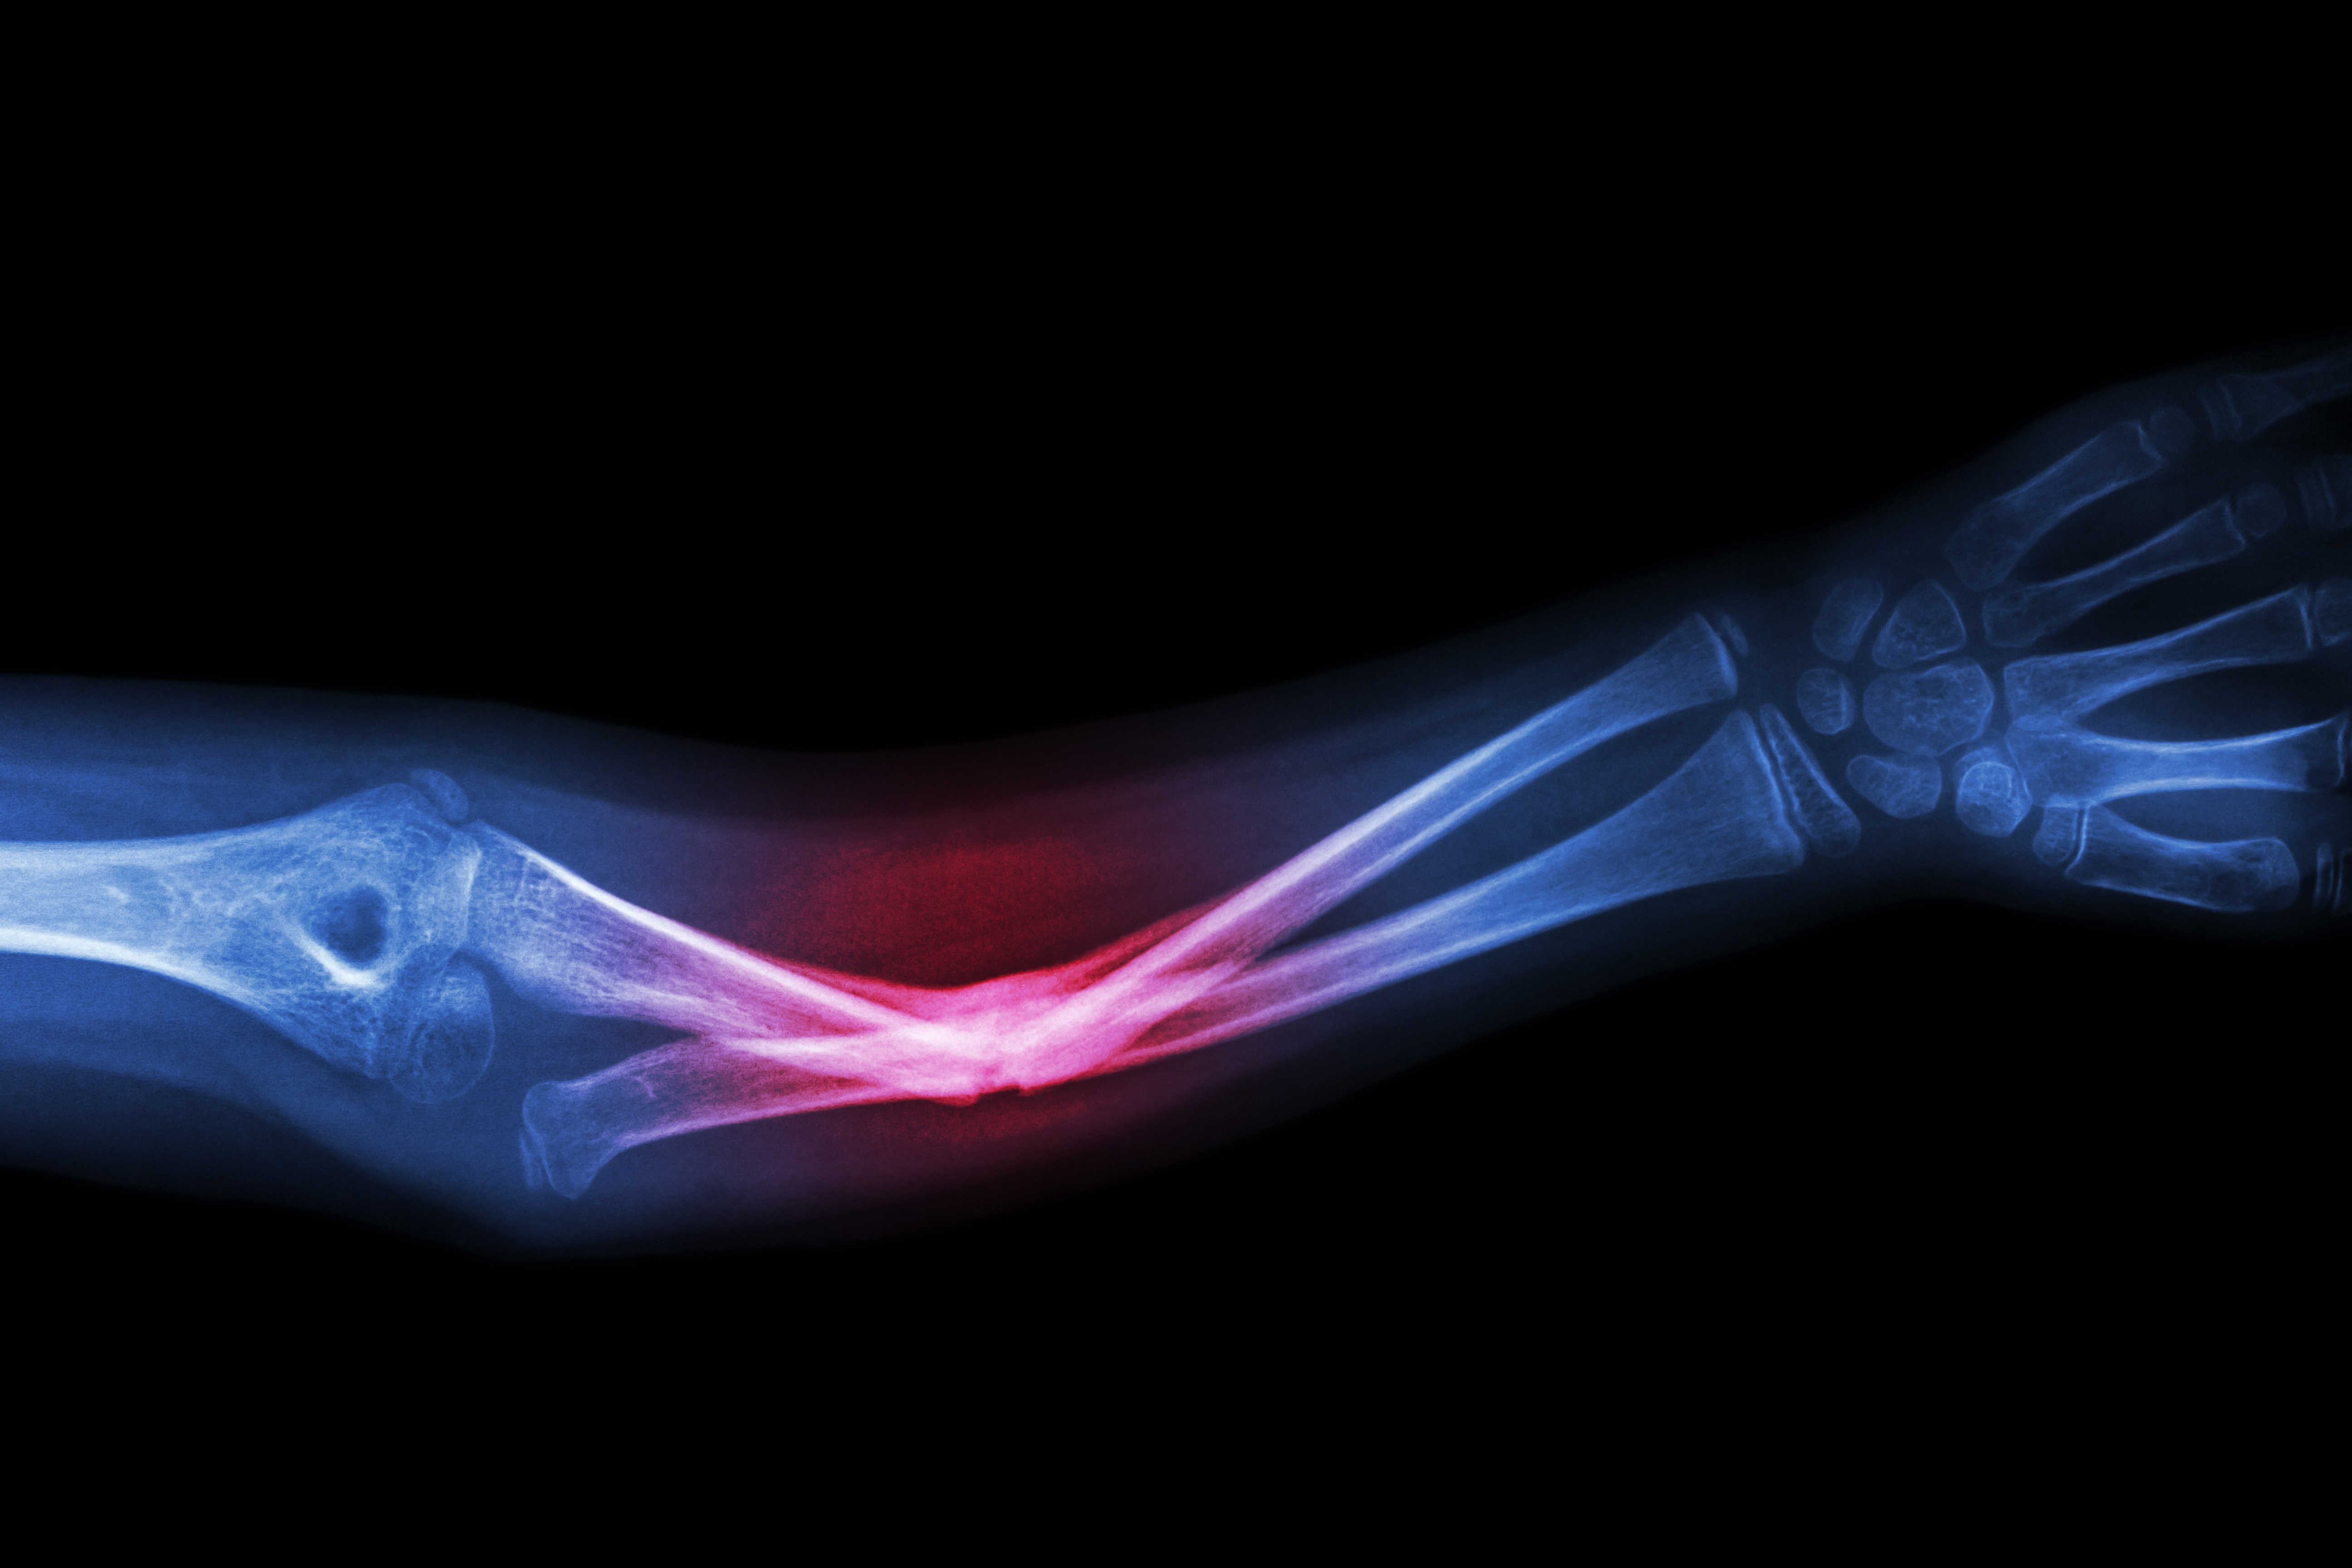

For the average baby not ultimately diagnosed with a moderate to severe form of Osteogenesis Imperfecta (OI)— a genetic disorder causing defects in quantity or quality of collagen— like Easton Elrod, fracturing a clavicle is not uncommon in a challenging vaginal birth. Due to positioning or a stuck shoulder or sometimes a large baby, this can occur. It is not an every day event, but happens enough that it is considered a consequence of normal birth trauma. When it does, the intervention is typically minimal as long as the bones are not displaced and impeding surrounding structures (a rare situation). Usually, the clinical course requires being aware of the area while clothing or moving the infant and being more gentle on that side as it heals -- all the while monitoring for continued symmetrical use and strength of the upper extremities.

Due to the wide spectrum of OI from mild to severe forms, in extreme cases the act of being born can be life-threatening. This brittle bone disease literally makes a newborn very fragile. In the extreme, it is not merely the pain of the many broken bones that is concerning but also what vital tissues they damage and organs they prevent from normally functioning. Crushing injuries can complicate the picture. Consider how challenging aerating the lungs can be if all the ribs are broken, for example.

Think about how a basic diaper change or a vigorous hug in a person with a more severe form of OI can elicit a fracture. Let alone recreational activities as a child ages.

The mainstay of treatment for OI includes medical, surgical and physical therapies designed to enhance function, prevent accidental trauma and provide supportive care. There is great variability in scope of disease. Having weaker bones is universal. Commonly, impaired growth is an issue as are bony deformities like bowing of the legs or curvature of the spine. Breathing can be affected, as can the heart, hearing and brittle nature of teeth.